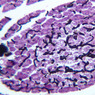

Scan slide B-36 (H&E [10x, 20x] [10x, 20x). Note that in this H&E preparation most of the pancreas consists of rather compactly arranged, darkly stained cells. The compact, darkly stained regions constitute the exocrine portion of the pancreas. (Of what organ does the exocrine pancreas remind you?) The endocrine portions of the pancreas consist of small bits, or islands, of more lightly stained tissue that is somewhat irregularly dispersed within the substance of the exocrine pancreas. Drawing on the name of their discoverer, the endocrine portions of the pancreas are known as the islets of Langerhans.

Using the high dry objective (B-36, H&E [40x, 40x-labeled]), study the structure of several acini. Note that the acinar cells are pyramidal in shape; note also that the acinar cells are clearly polarized: their basal cytoplasm (periphery of acinus) is quite basophilic, owing to large accumulations of RER, whereas their apical cytoplasm contains many acidophilic granules (zymogen granules) (B-36, H&E [10x, 20x, 40x-labeled]).

Now turn your attention to the system of pancreatic ducts. As you look for duct elements, bear in mind that the nuclei of duct cells tend to stain more lightly and to have less prominent nucleoli than do those of acinar cells. Begin by studying a number of different acini until you have identified several examples of centroacinar cells, which represent the initial segment of the duct system. Centroacinar cells are usually evident as lightly stained nuclei that lie, individually or in clusters of two or three, near the center of an acinus. Now look along the boundaries between acini for intercalated ducts (B-36, H&E [10x, 20x, 40x-labeled] [10x, 20x, 40x]), which appear in longitudinal section as trains of elongate, lightly stained nuclei and in transverse section as closely spaced, lightly stained nuclei surrounding a small lumen. Intercalated ducts drain into intralobular ducts, which are distinguished by their larger diameter. It is best to use the 10X objective as you begin your search for intralobular ducts (B-36, H&E [10x, 20x, 40x-labeled] [10x, 20x, 40x]). You want to be on the lookout for arrays of closely spaced nuclei surrounding a lumen. Conclude your study of the duct system by examining the connective tissue between pancreatic lobules for interlobular ducts, which may vary in caliber and epithelial lining (B-36, H&E [10x-labeled, 20x, 40x]).